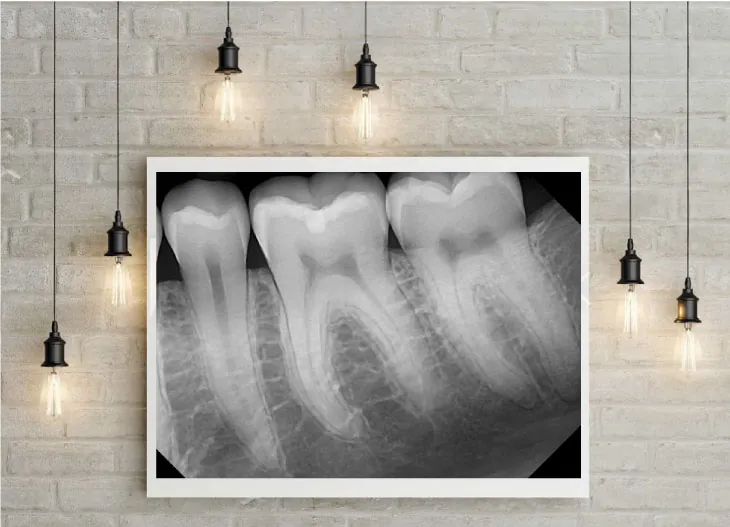

Using Creativity To Get The Best Digital X-Rays